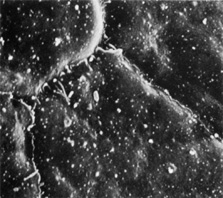

effects of colchicine, ether, cocaine, and ephedrin. Bull Johns Hopkins Hosp 73:143, 1943 23. Gipson IK, Spurr-Machaud S, Tisdale A, et al: Redistribution of the hemidesmosome components alpha 6 beta 4 integrin

and bullous pemphigoid antigens during epithelial wound healing. Exp Cell Res 207:86, 1993 24. Shams NB, Hanninen LA, Chaves HV, et al: Effect of vitamin A deficiency on the adhesion of rat corneal epithelium